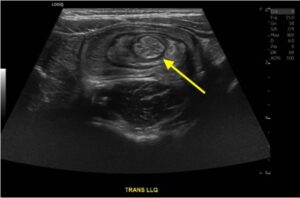

Colocolic Intussusception. Abdominal Ultrasound, Annotated. JETem 2024

Colocolic Intussusception. Abdominal Ultrasound Annotated. JETem 2024